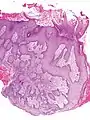

- Pseudoepitheliomatous hyperplasia (PEH) is a benign condition characterized by hyperplasia of the epidermis and epithelium of skin appendages,[31] with irregular squamous strands extending down into the dermis,[32] and closely simulating squamous cell carcinoma (SCC).[31]

Pseudoepitheliomatous hyperplasia (PEH), low magnification, with acanthotic squamous epithelium with irregular thick finger-like downgrowths into the underlying dermis.

PEH, high magnification, with reactive-appearing squamous downgrowths with no significant cytologic atypia.